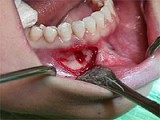

1.组图是牙龈瘤患者,有关此病的描述不正确的是 ( )![]() ![]() ![]() ![]() |